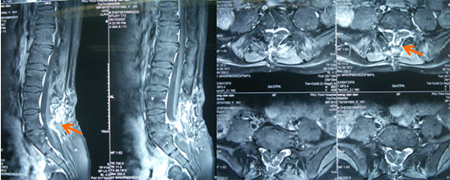

女性,17岁,劳累后腰部疼痛3年。入院查体:神情语利,卧位,双眼活动充分、双瞳等约2.0mm、光反射灵敏,面纹称,伸舌中,颈抵抗(-)。四肢可自主活动,鞍区针刺痛觉减退。B超:膀胱残余尿量10ml。术前图片:

术中发现L4-5椎板异常增生肥厚,L5椎板伸入椎管内形成骨嵴,脊髓圆锥低位在L4水平,L4以下肿瘤组织为多种成份,近端为脂肪组织,S1水平分为两种肿瘤成份,内侧为清亮粘液状物、外侧为珍珠样角化物。